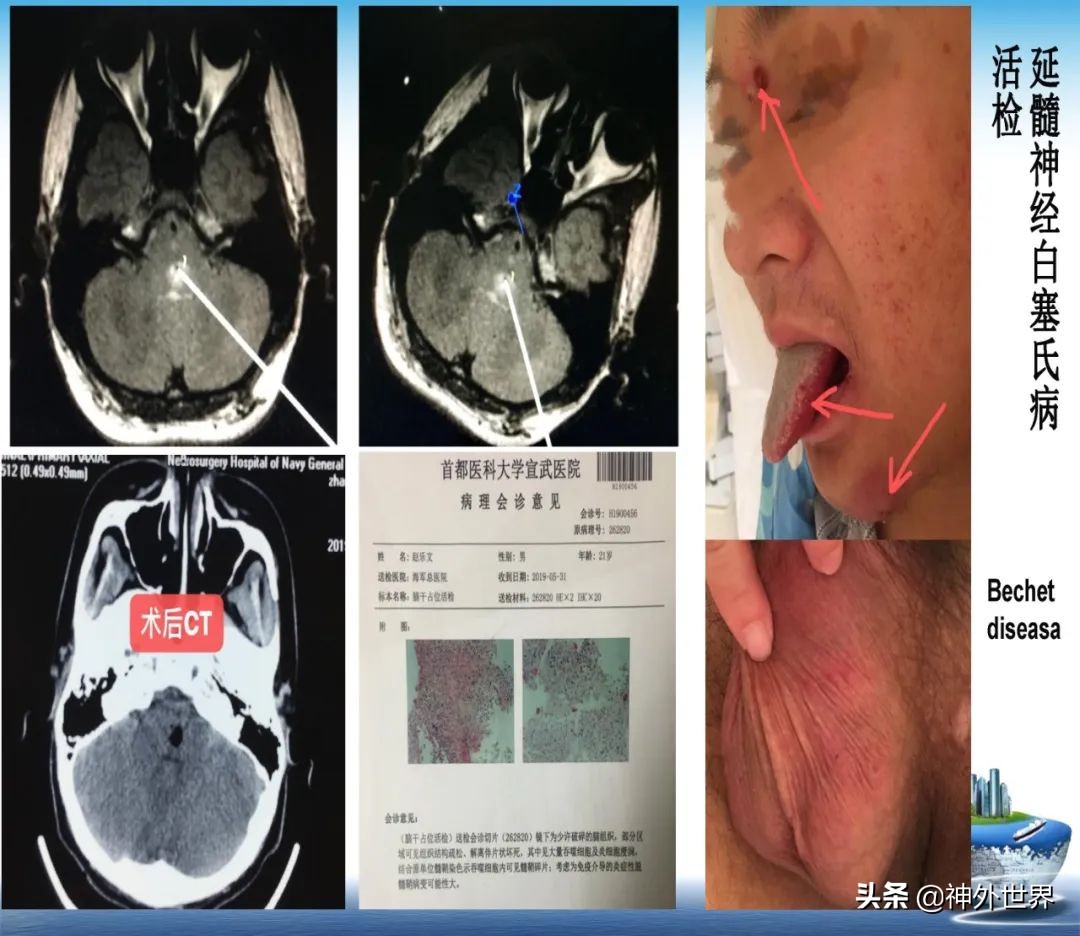

专业方向:颅内肿瘤的显微外科手术切除,颅咽管瘤综合治疗具有特色;在立体定向脑内病灶活检、立体定向清除脑干血肿、立体定向间质内放疗、机器人辅助神经外科手术方面具有专长。